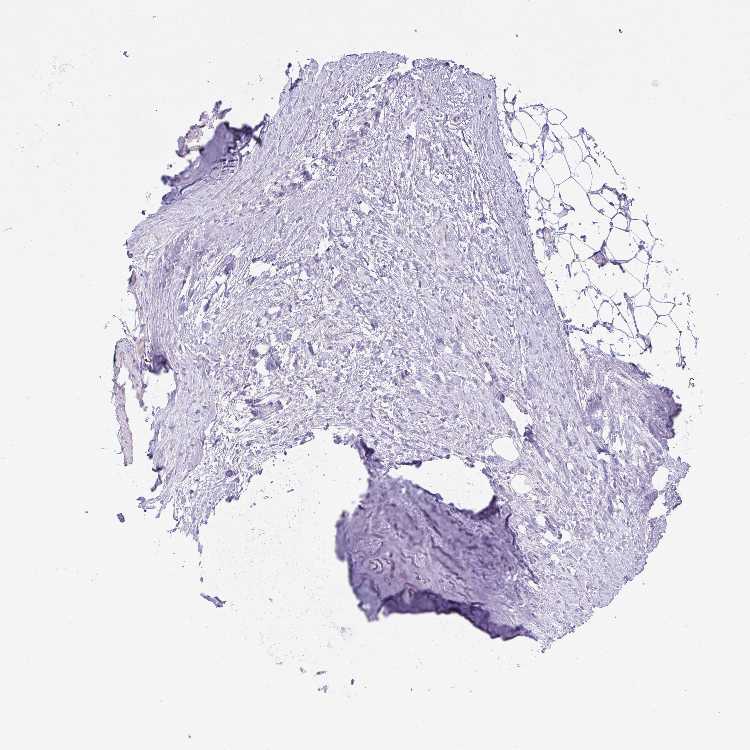

TISSUE PRIMARY DATA SOFT TISSUE Show tissue menu

SOFT TISSUE - Expression summary

SOFT TISSUE 1 - Antibody stainingi

Antibody staining in the annotated cell types in the current human tissue is reported as not detected, low, medium, or high, based on conventional immunohistochemistry profiling in selected tissues. This score is based on the combination of the staining intensity and fraction of stained cells.

Each image is clickable and will lead to virtual microscopy that enables deeper exploration of all samples and also displays staining intensity scores, fraction scores and subcellular localization as well as patient and tissue information for each sample.

Antibody HPA045704Antibody HPA049497Antibody HPA051675

Chondrocytes LowNot detectedLow

Fibroblasts Not detectedNot detectedLow

Peripheral nerve Not detected-Not detected